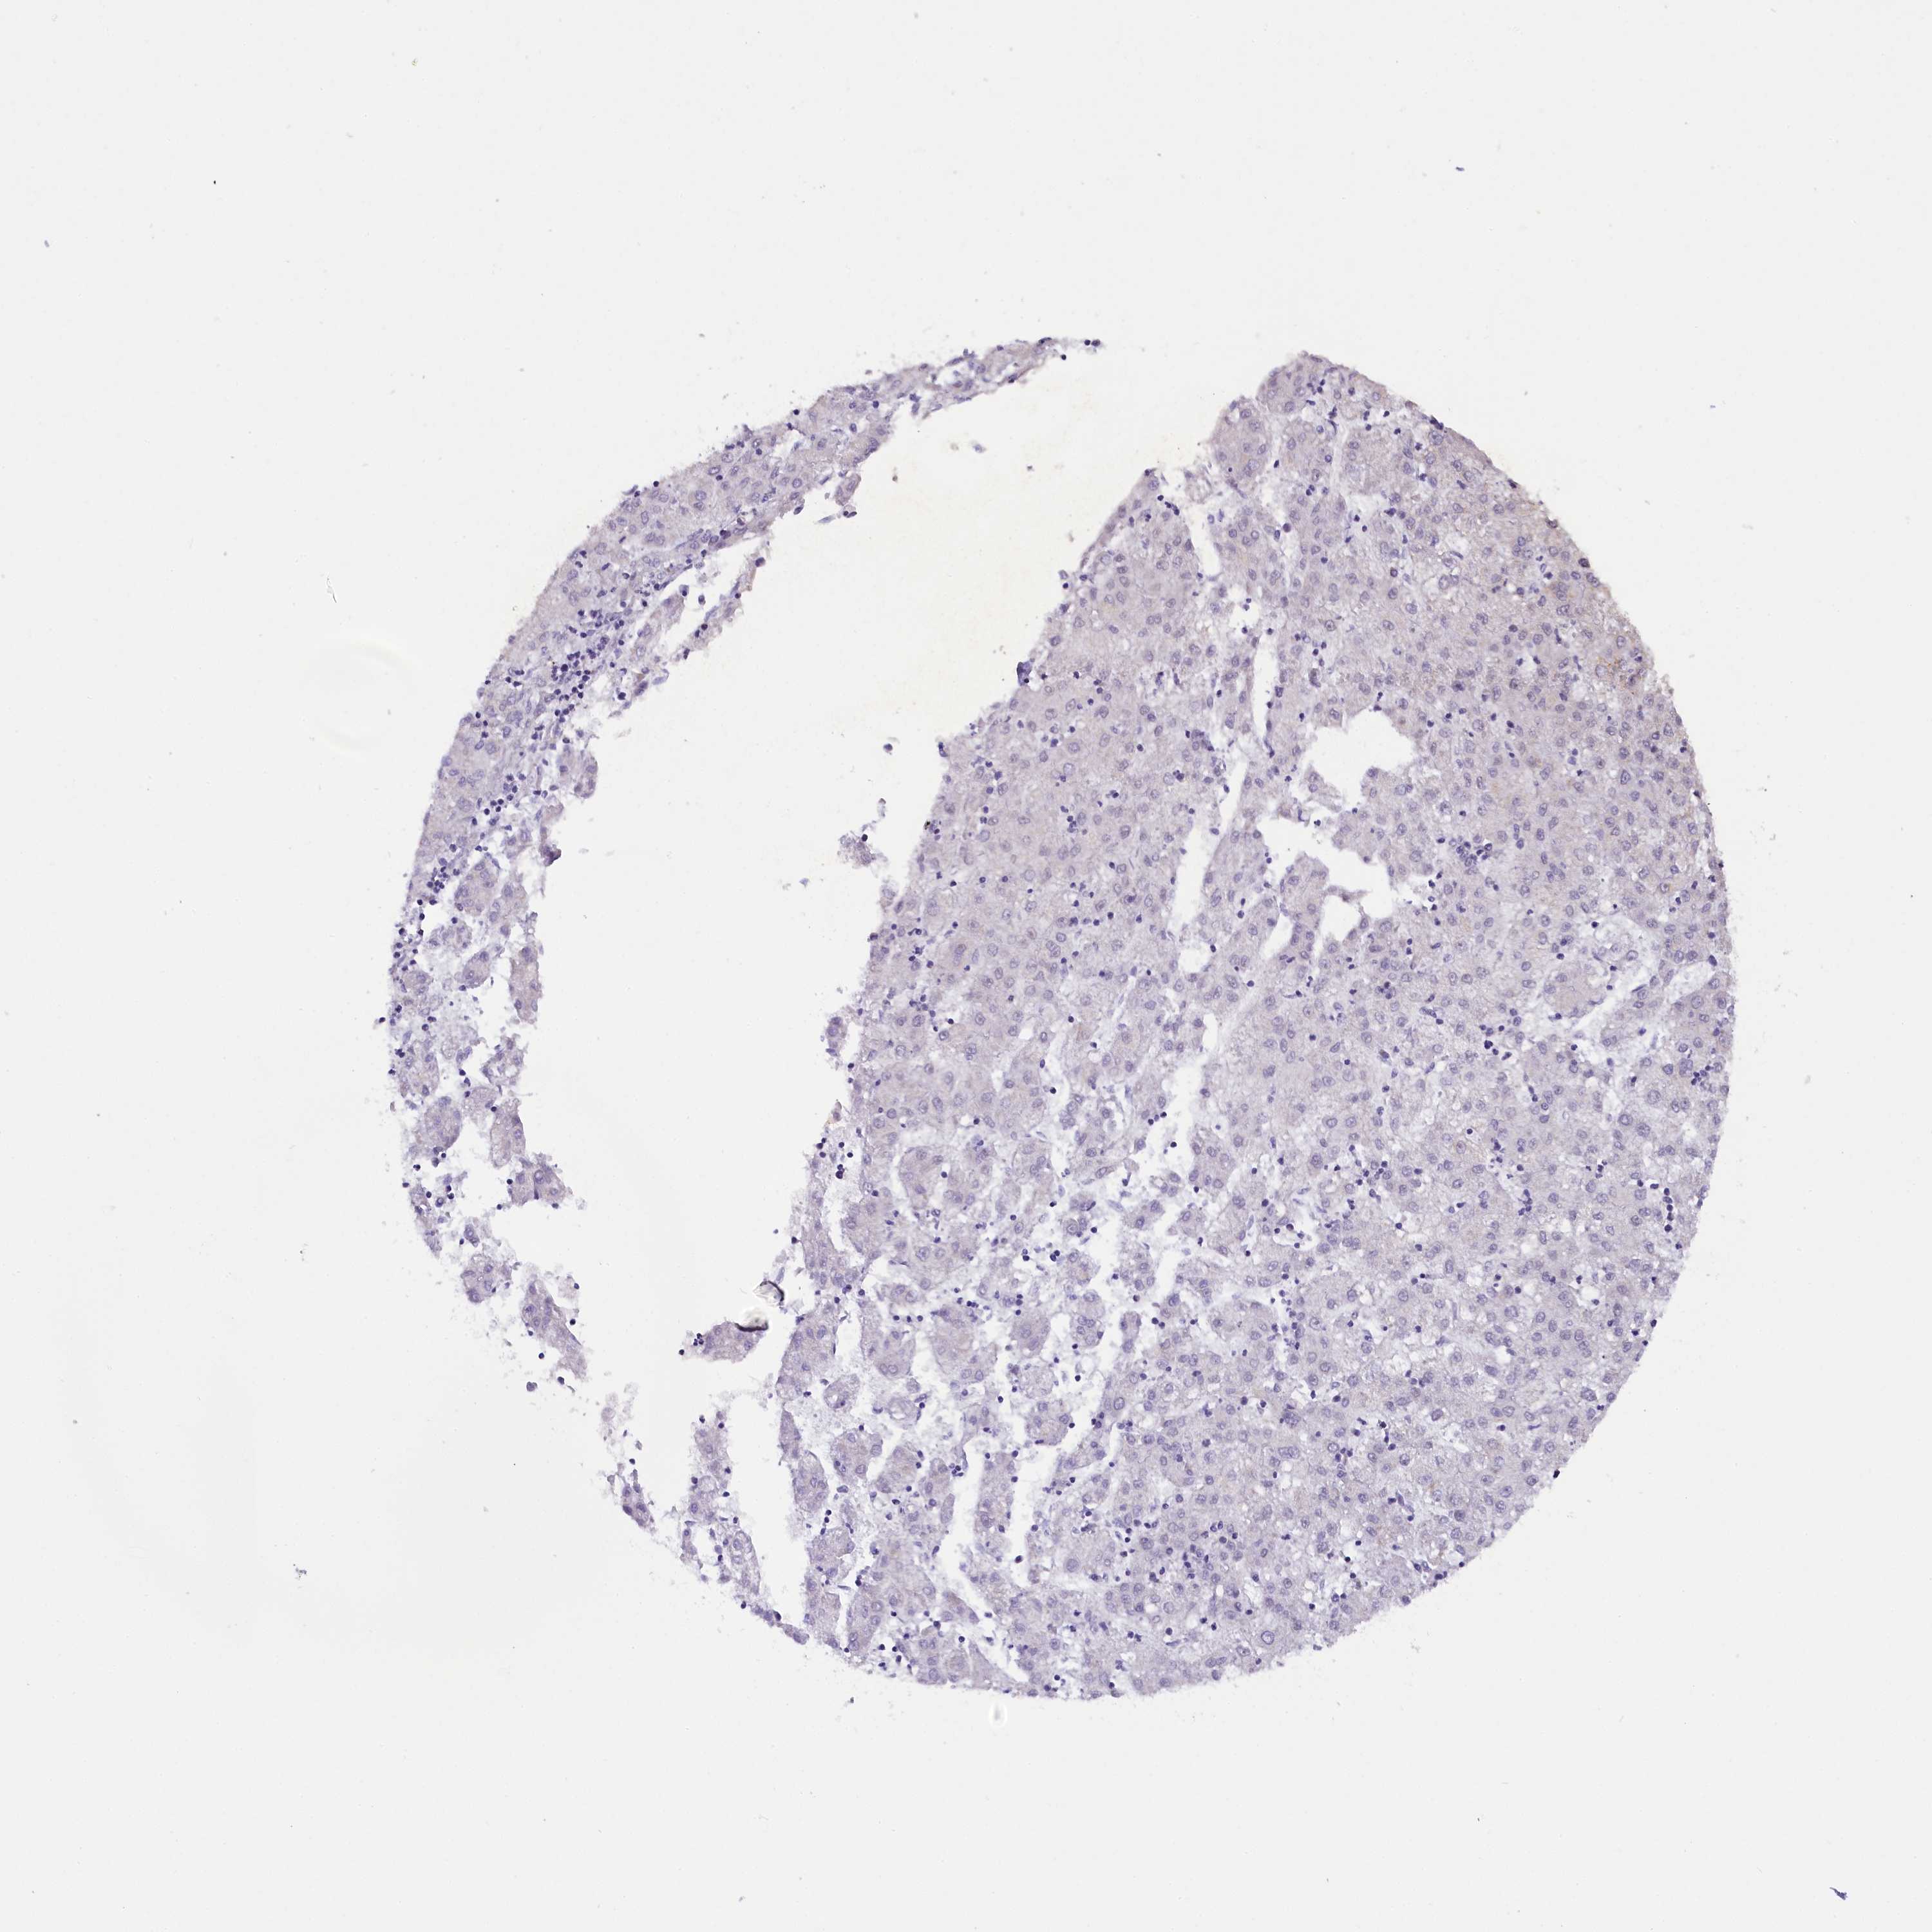

LIVER CANCER - Protein expressioni

A mouse-over function shows sample information and annotation data. Click on an image to view it in a full screen mode. Samples can be filtered based on level of antibody staining by selecting one or several of the following categories: high, medium, low and not detected. The assay and annotation is described here.

Note that samples used for immunohistochemistry by the Human Protein Atlas do not correspond to samples in the TCGA dataset.

Antibody stainingi

Antibody staining in the annotated cell types in the current human tissue is reported as not detected, low, medium, or high, based on conventional immunohistochemistry profiling in selected tissues. This score is based on the combination of the staining intensity and fraction of stained cells.

Each image is clickable and will lead to virtual microscopy that enables deeper exploration of all samples and also displays staining intensity scores, fraction scores and subcellular localization as well as patient and tissue information for each sample.

Antibody HPA042411

Antibody HPA049031

Staining

High

Medium

Low

Not detected

Intensity

Strong

Moderate

Weak

Negative

Quantity

>75%

75%-25%

<25%

None

Location

Nuclear

Cytoplasmic/membranous

Cytoplasmic/membranous,nuclear

Cholangiocarcinoma

Carcinoma, Hepatocellular, NOS